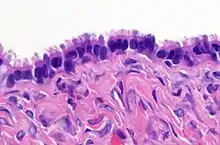

Histopathology of lining of a benign serous tumor of the ovary. Benign serous ovarian tumors are thin walled unilocular cysts that are lined by ciliated pseudostratified cuboidal or columnar epithelium.[14]

• lined by tall, columnar, ciliated epithelial cells

• filled with clear serous fluid

• the term serous which originated as a description of the cyst fluid has come to be describe the particular type of epithelial cell seen in these tumors

• may involve the surface of the ovary